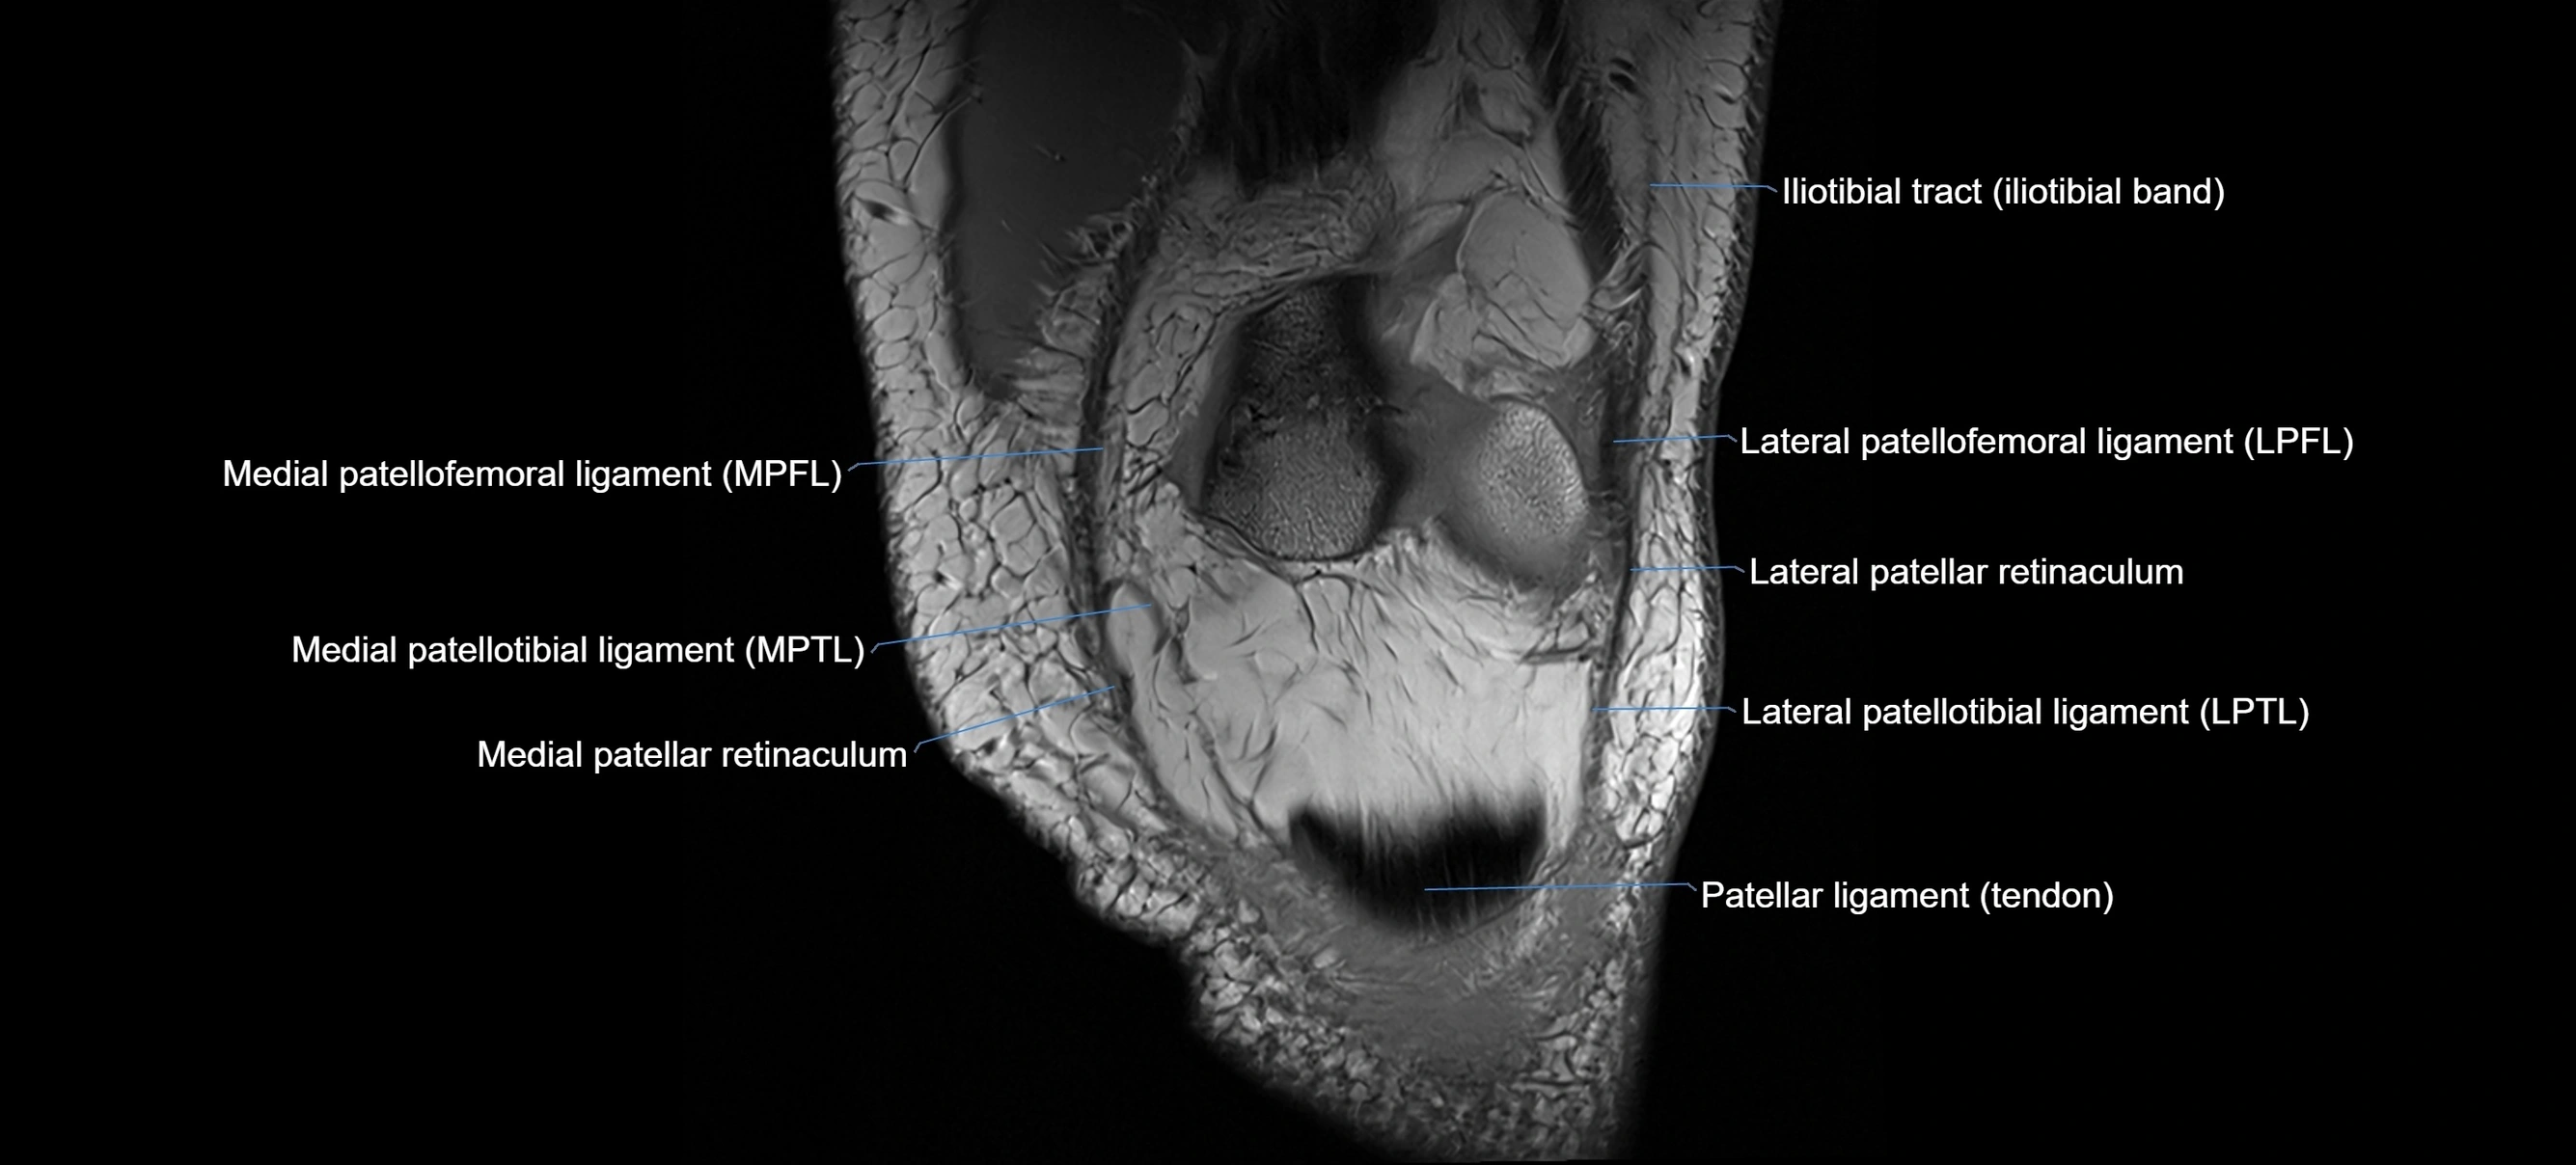

MRI images

image